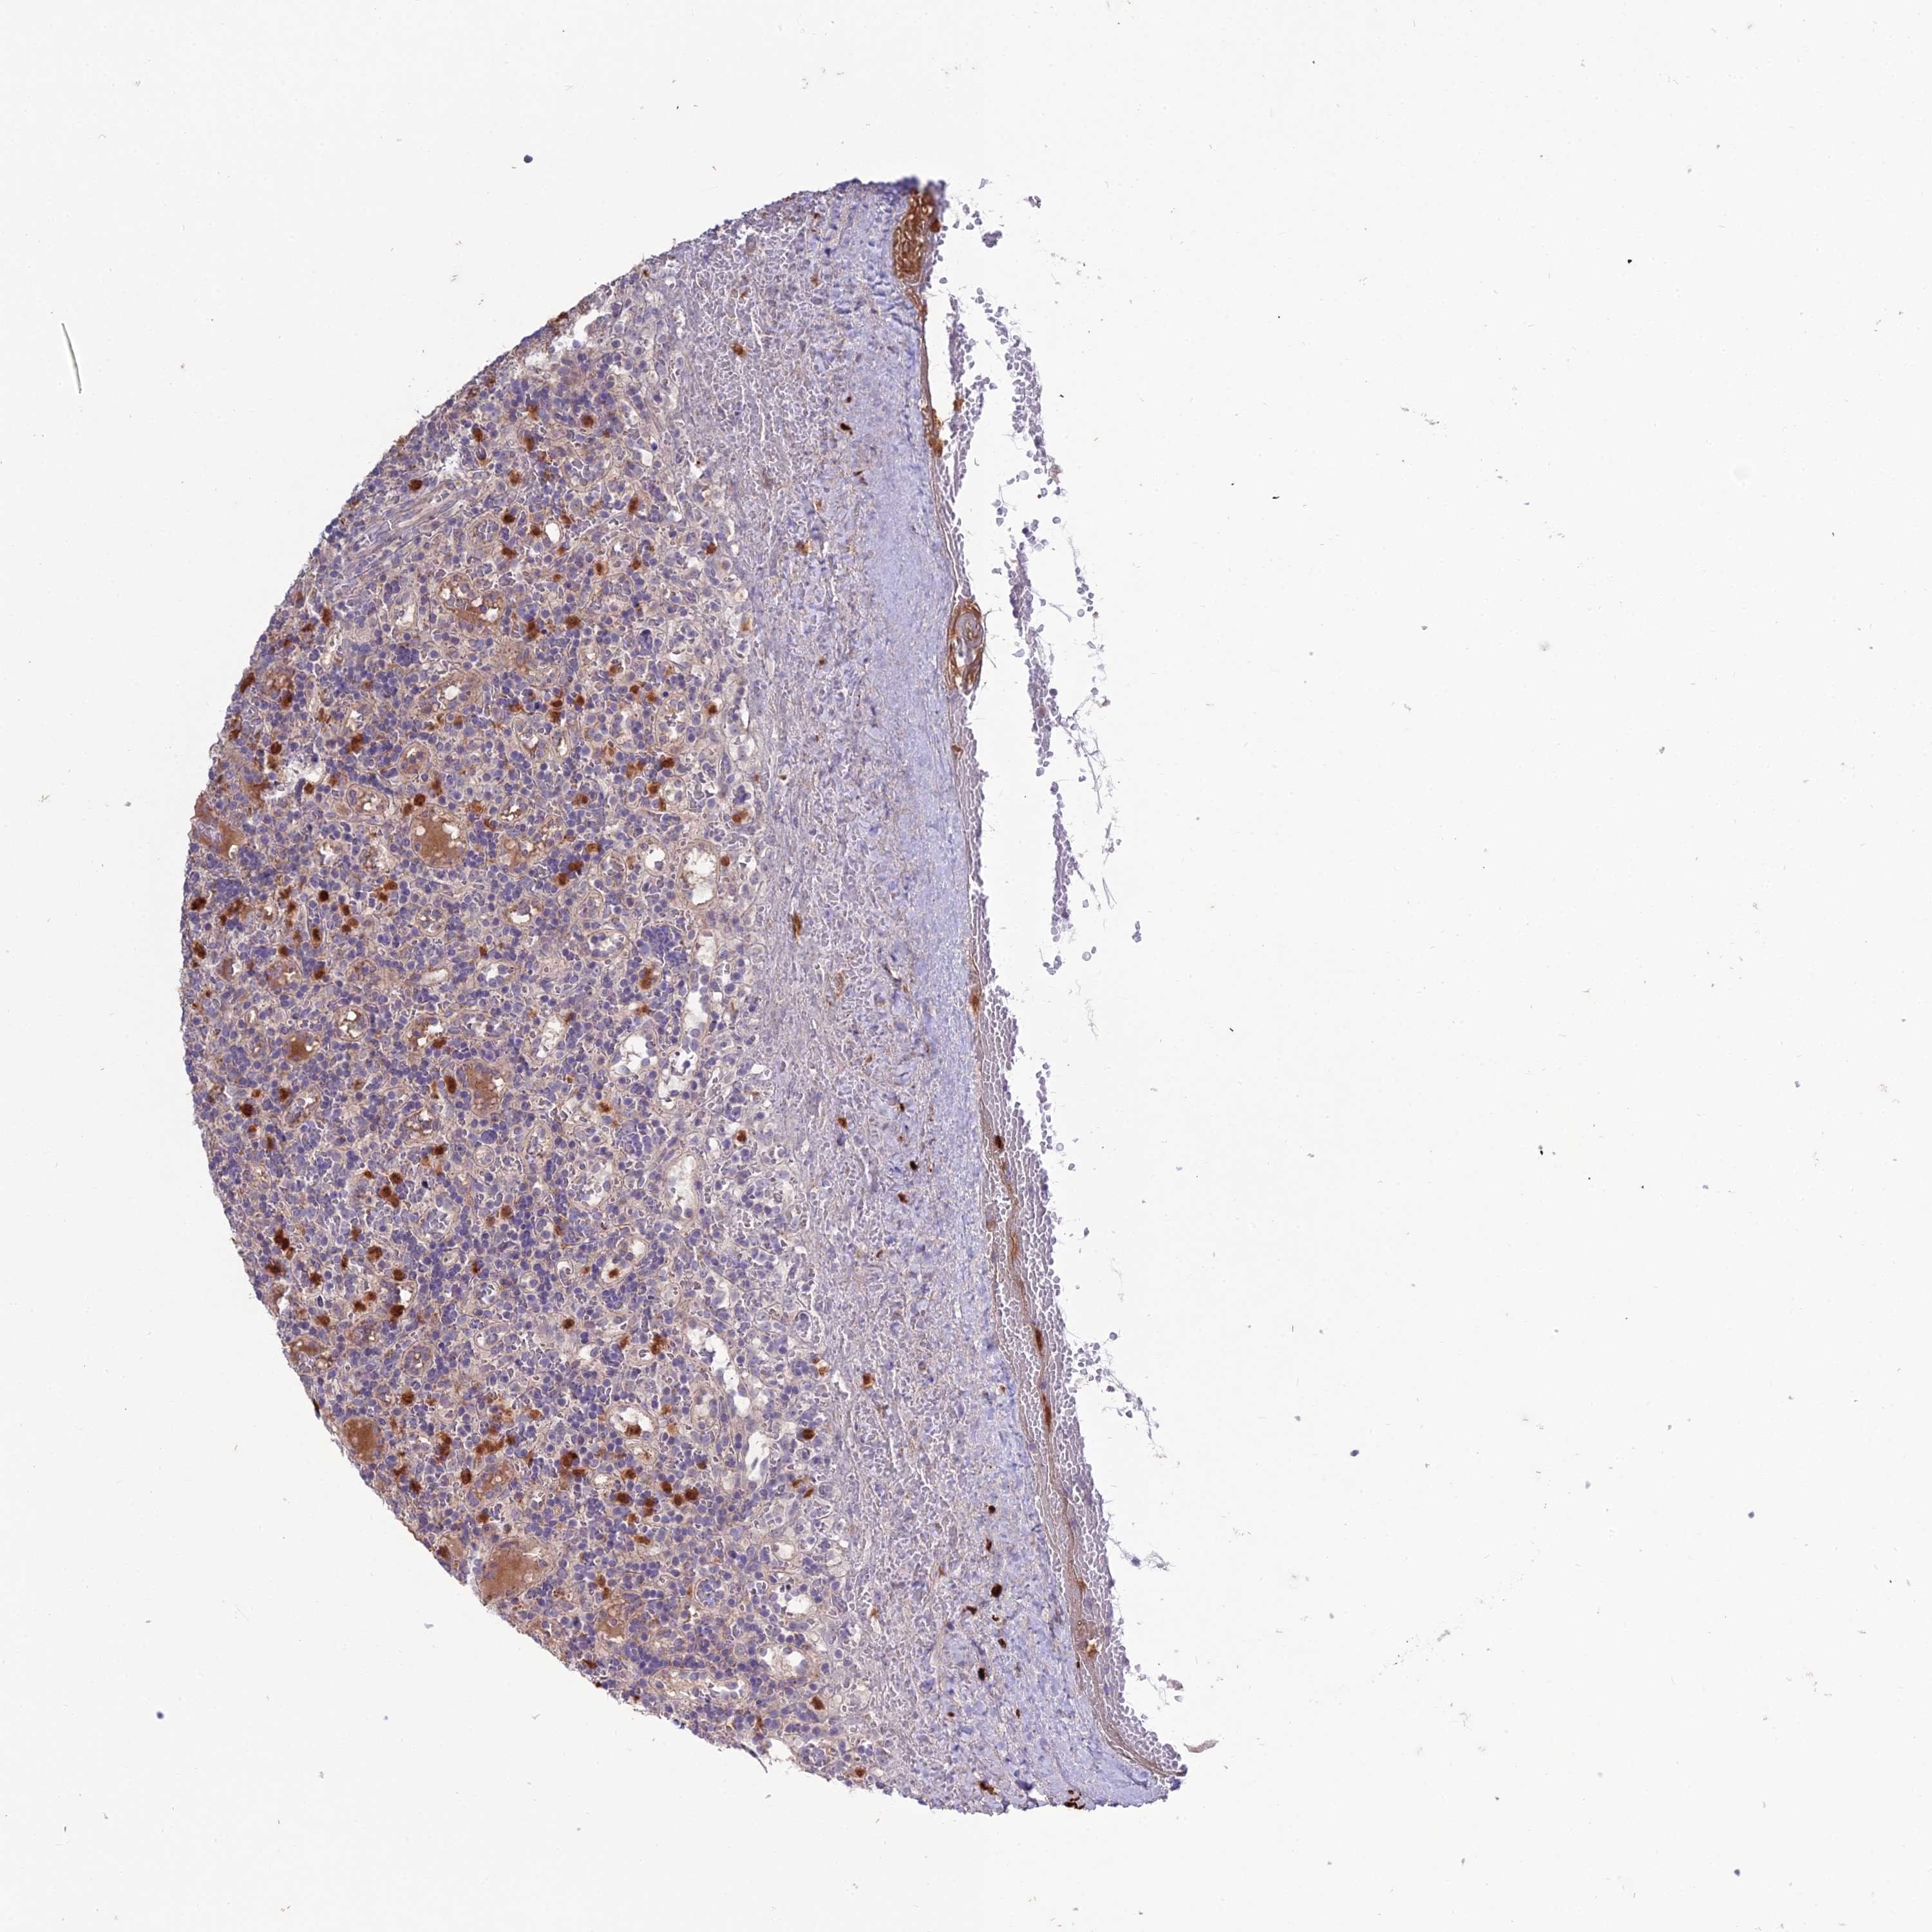

LYMPHOMA - Protein expressioni

A mouse-over function shows sample information and annotation data. Click on an image to view it in a full screen mode. Samples can be filtered based on level of antibody staining by selecting one or several of the following categories: high, medium, low and not detected. The assay and annotation is described here.

Antibody stainingi

Antibody staining in the annotated cell types in the current human tissue is reported as not detected, low, medium, or high, based on conventional immunohistochemistry profiling in selected tissues. This score is based on the combination of the staining intensity and fraction of stained cells.

Each image is clickable and will lead to virtual microscopy that enables deeper exploration of all samples and also displays staining intensity scores, fraction scores and subcellular localization as well as patient and tissue information for each sample.

Antibody HPA045477

Staining

High

Medium

Low

Not detected

Intensity

Strong

Moderate

Weak

Negative

Quantity

>75%

75%-25%

<25%

None

Location

Nuclear

Cytoplasmic/membranous

Cytoplasmic/membranous,nuclear

Hodgkin's disease, NOS

Malignant lymphoma, non-Hodgkin's type, High grade

Malignant lymphoma, non-Hodgkin's type, Low grade